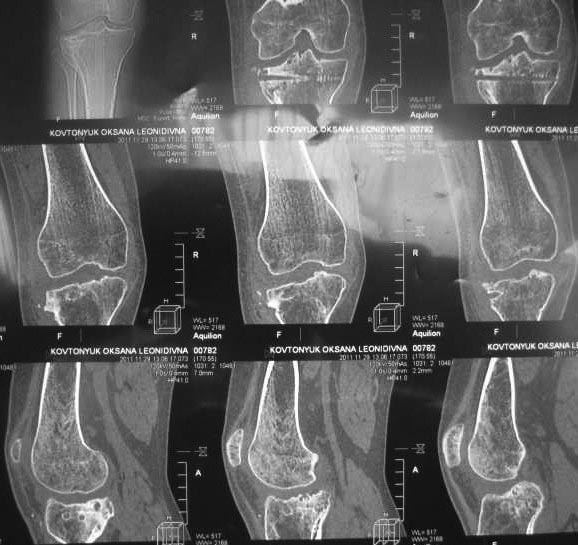

Надо на КТ посмотреть для планирования.

Мне кажется, нужно понять характер полученного перелома тибиального плато, степень и характер смещения отломков, есть ли дефект поверхности тибиального плато. На все это ответит КТ исследование! Тогда Вы тут остеотомией ничего не получите. Дообследуйте пациентку.

Жалобы на деформацию и нарушение функции правого коленного сустава .Внешний вид –вальгусная деформация на уровне коленного сустава .Коленный сустав стабильный, надколенник при сгибании в правильном положении.

Планируэм провести остеотомию на уровне проксимального метафиза большеберцовой кости .